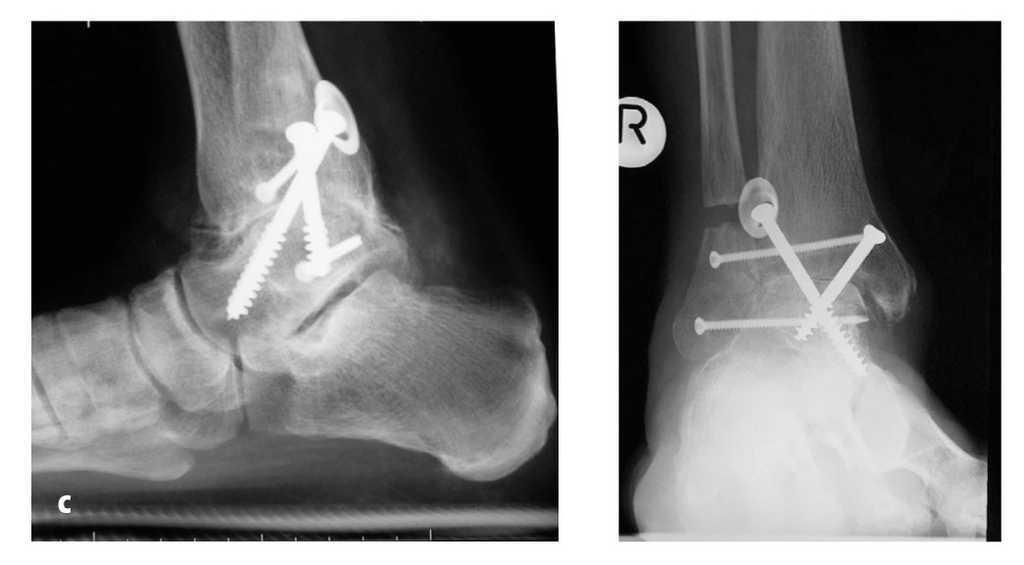

WebDiscapacidad por Artrosis de Tobillo o Rodilla La medición se centrará en la limitación de movimiento y en la anquilosis , en caso de existir. Todo ellos según las tablas 37 y 38 -si. WebLa incapacidad permanente por artrodesis es una realidad médico – legal cada vez más frecuente a la hora de reclamar la declaración de nuestro grado de incapacidad. WebLa artrodesis, por tanto, es un procedimiento, la mayoría de las veces quirúrgico, que persigue dejar sin movilidad definitivamente a una articulación. En el.

ARTRODESIS | Qué es, por qué se realiza, complicaciones, cuidados y tratamiento fisioterapéutico